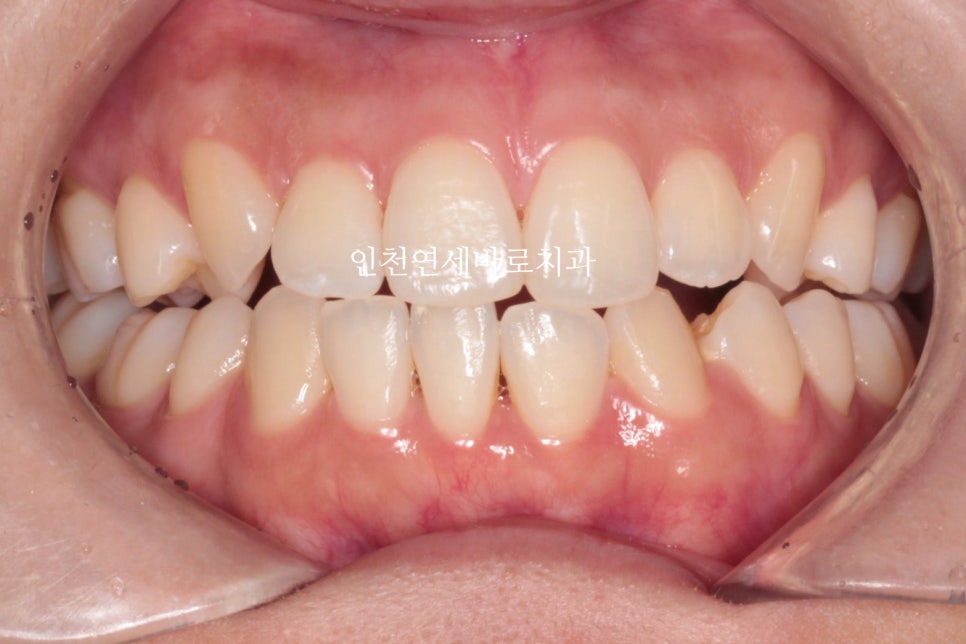

지난 주 마무리된 모습

결손치아가 있지만 교합은 문제없게 마무리

그리고 중요한 앞모습

과정이야 힘들고 오래걸리고 장치도 교체하고 어려웠지만

목표한바는 모두 달성한 치료입니다.